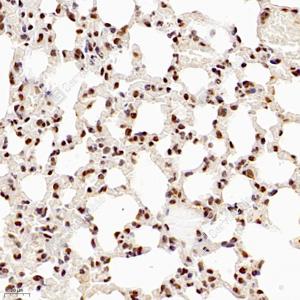

IHC检测NSFL1C蛋白(货号 GB112604). 样品: 小鼠肺, 4%多聚甲醛 (货号G1101) 固定12-24小时. 抗原修复: 柠檬酸抗原修复液(干粉, pH 6.0) (G1201), 98℃, 20分钟. —抗: 1: 700稀释, 4℃ 孵育过夜. 二抗: HRP标记山羊抗兔IgG (H+L) (货号GB23303), 1: 200稀释, 室温孵育1小时. |